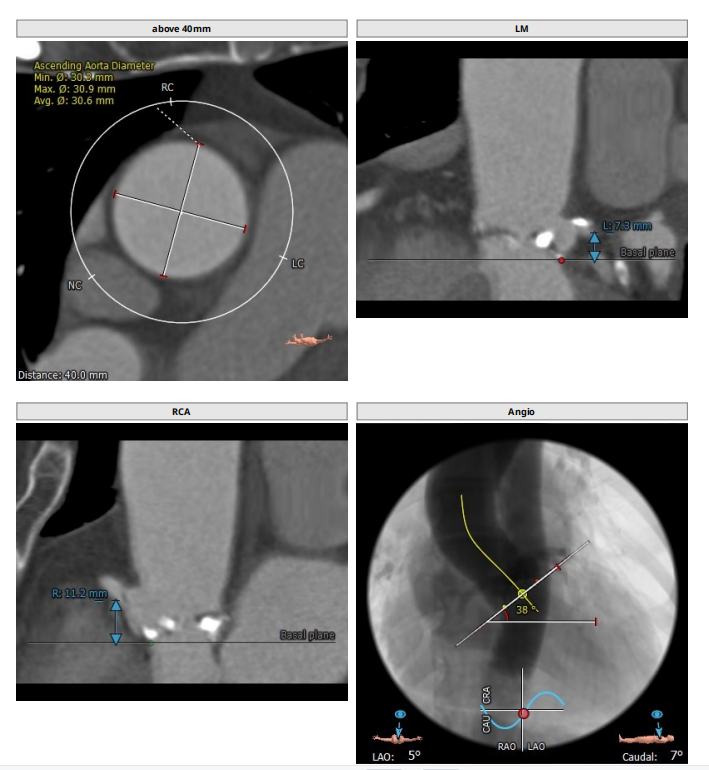

术前CT分析

三叶瓣,轻中度钙化,右无疑似融合,左冠开口高度低,右冠开口高度不高,法式窦结构不大,左室大小可,升主动脉未见明显扩张。小窦,小瓣环,准备瓣膜型号L23。

术前医院高度重视,组织多科室专家结合患者病情,以及存在高龄、解剖结构特殊等诸多风险进行深入分析、反复讨论后,充分准备并制定应急预案。心内科团队结合超声及CT测量数值(主动脉根部及冠脉高度)及患者病情,拟定应用Guidezilla延长导管进行冠脉保护,应用20F戈尔长鞘,送至升主动脉后经导管置入VenusA-Plus®可回收输送系统,选用18mm球囊预扩张,经由右侧股动脉入路植入L23型号瓣膜成功完成此次手术。